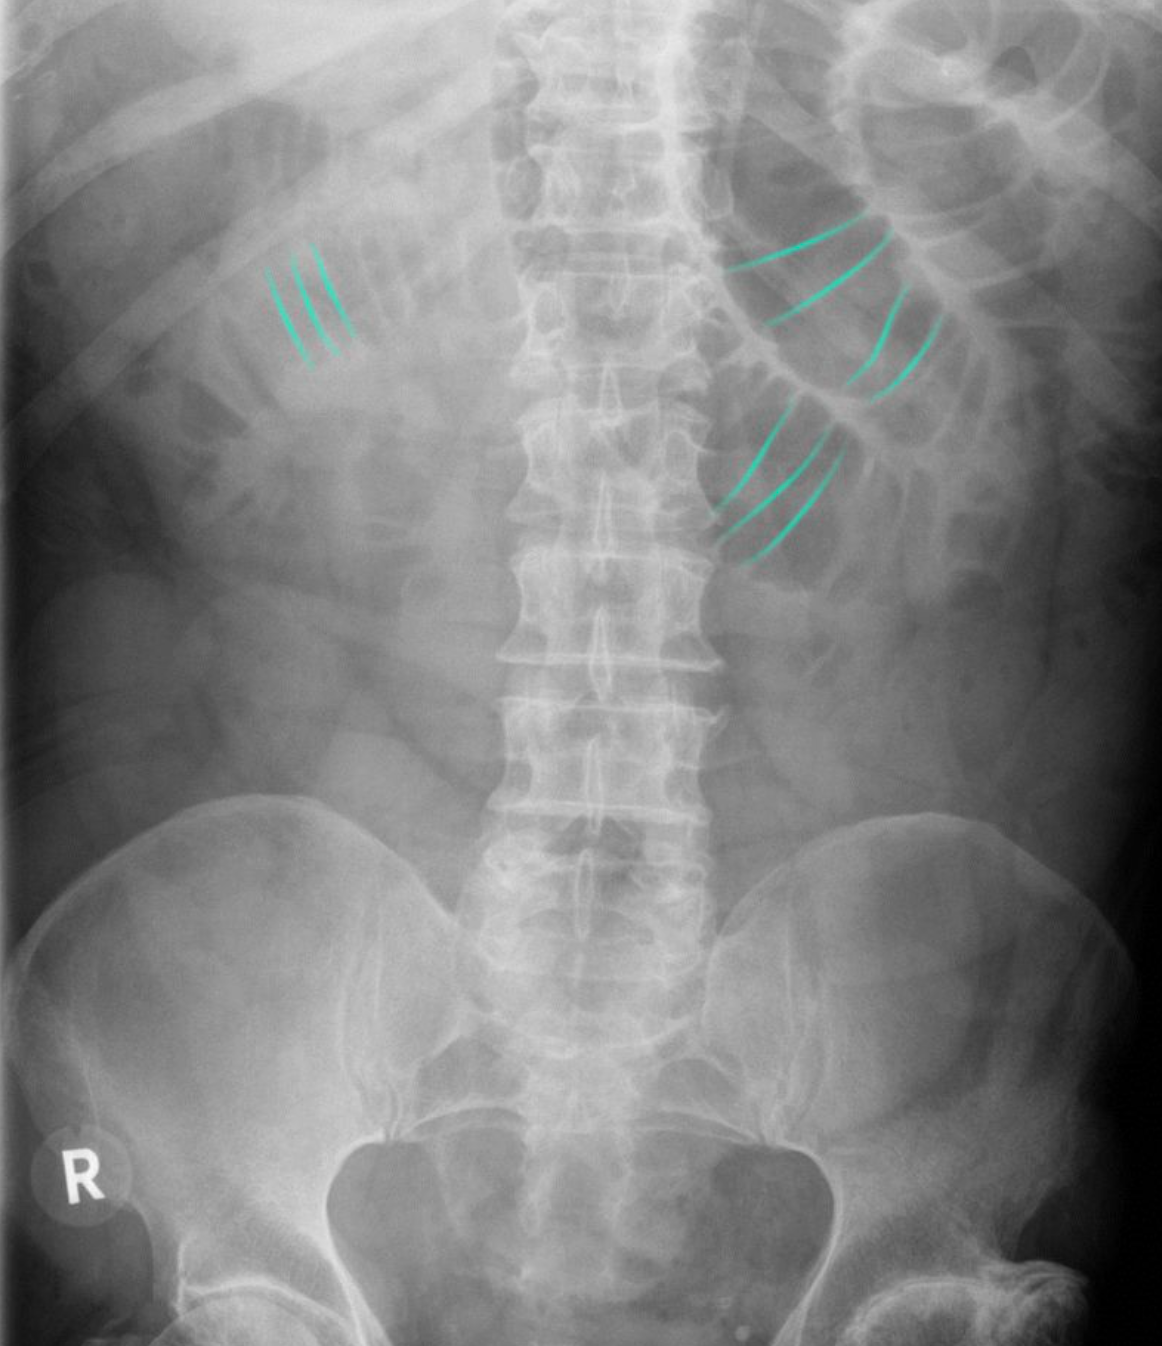

Bilateral hyperinflation and right lung consolidation

X-ray chest (AP view) of a child with viral bronchiolitis and focal pneumonia

Bilateral perihilar peribronchial thickening (examples of bronchi indicated by green lines) is accompanied by hyperinflation with diaphragmatic depression (indicated by white lines and arrow). In the right lung, a superimposed area of consolidation from pneumonia (red overlay) is associated with atelectasis and ipsilateral mediastinal shift (indicated by black arrow).

Black outline: trachea; white dashed line: physiological position of left hemidiaphragm